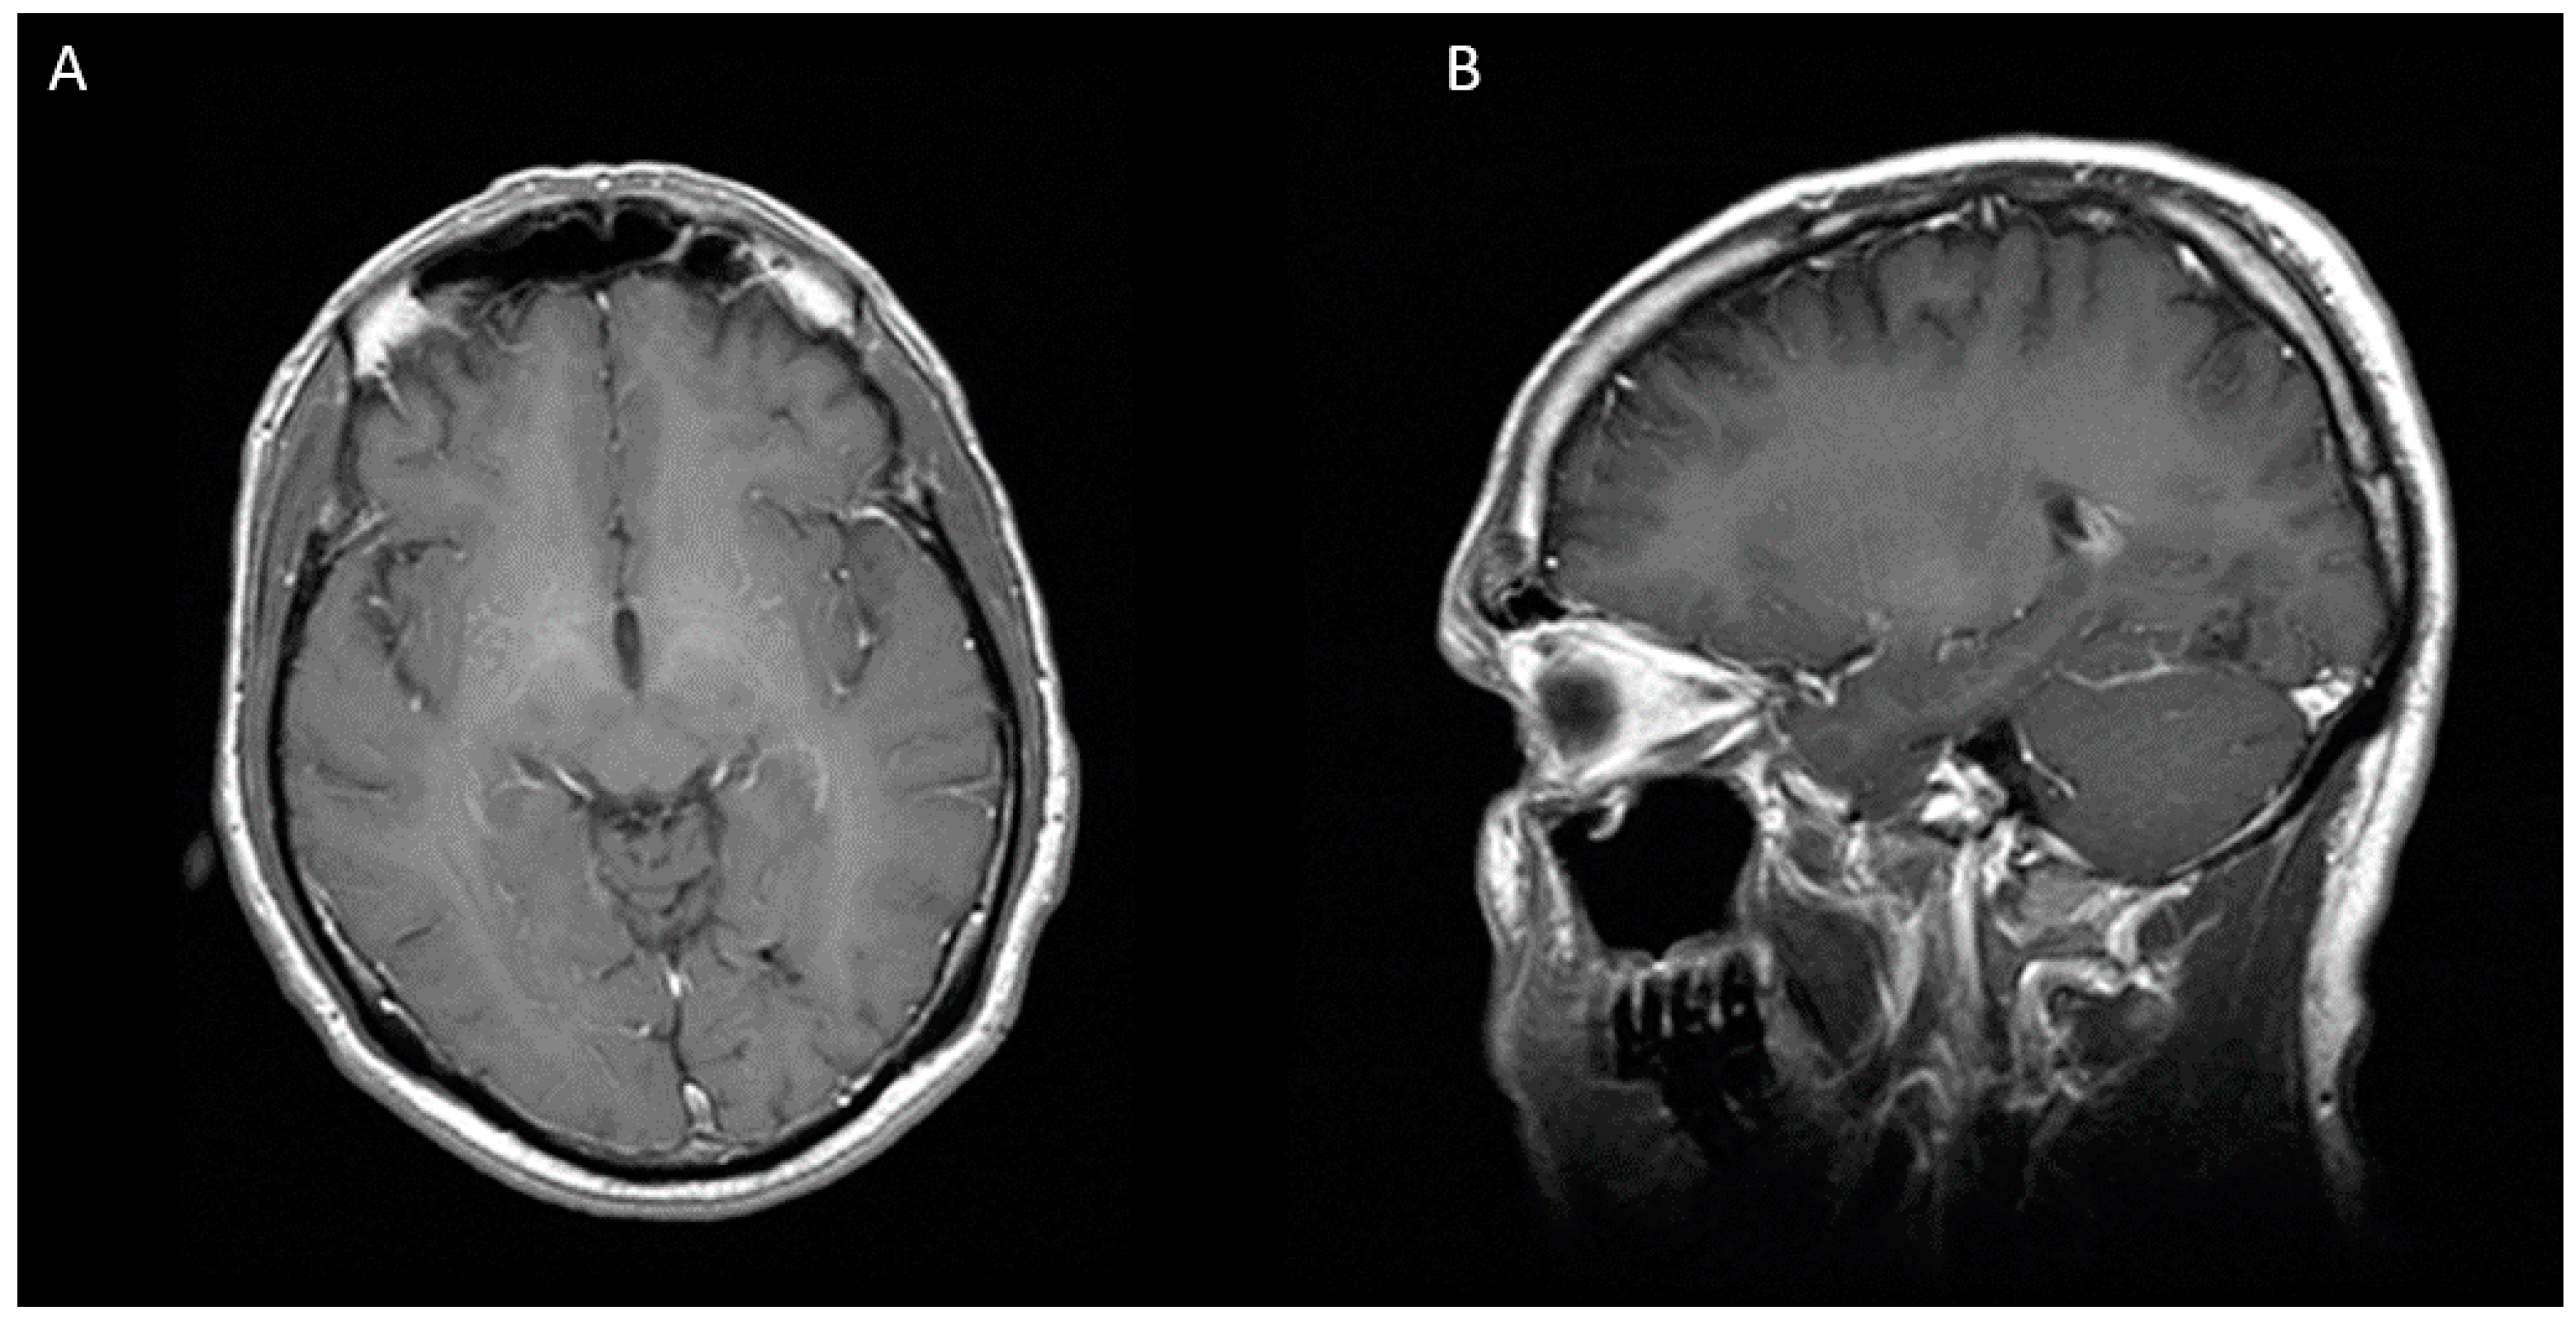

Figure 1.

MRI showing a multilobulated and multiseptated lesion of 31 × 31 × 26 mm with peripheral enhancement in the left occipital lobe. (A) Axial view (B) Sagittal view.